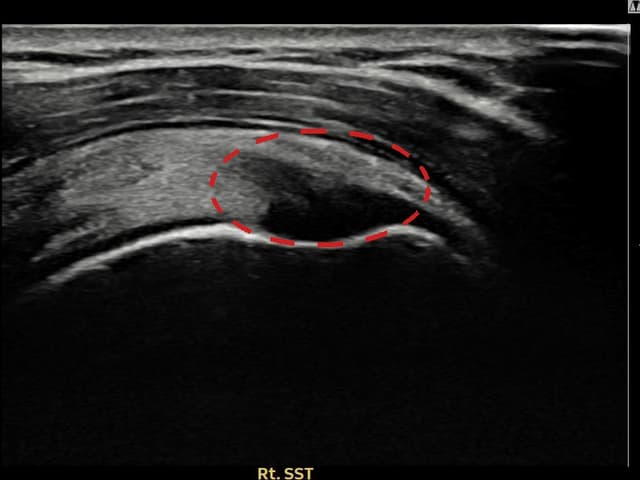

[촬영시기:23.09.01~23.11.03]

[어깨인대 축소봉합술] 우측 어깨 통증이 수개월간 지속되어 내원하셨습니다.